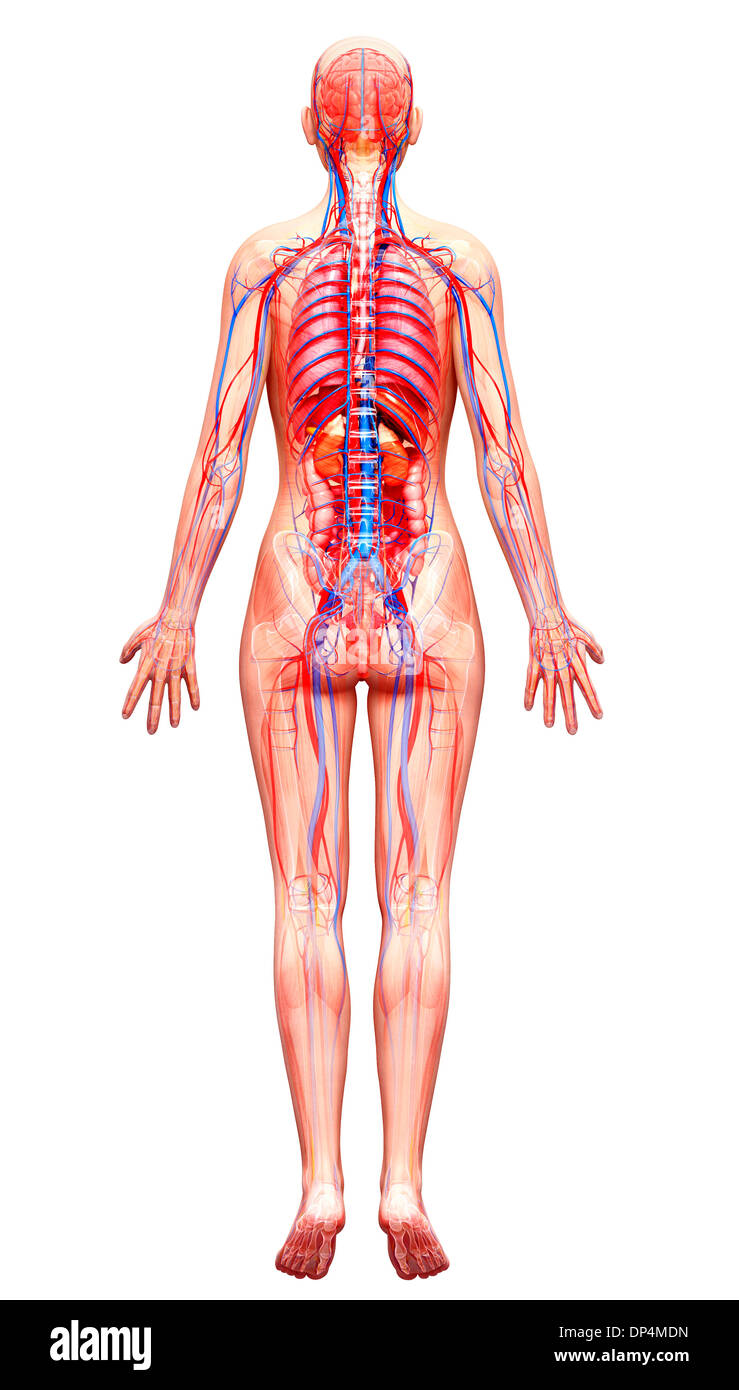

, Artwork Banque D'Imageshttps://www.alamyimages.fr/image-license-details/?v=1https://www.alamyimages.fr/artwork-image65257409.html

, Artwork Banque D'Imageshttps://www.alamyimages.fr/image-license-details/?v=1https://www.alamyimages.fr/artwork-image65257409.htmlRFDP4MDN–, Artwork